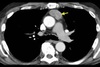

6

Homem, 60anos, dor torácica e abdominal de forte intensidade há 2 horas.

Dissecção de aorta abdominal, com artéria renal direita oriunda da luz falsa.